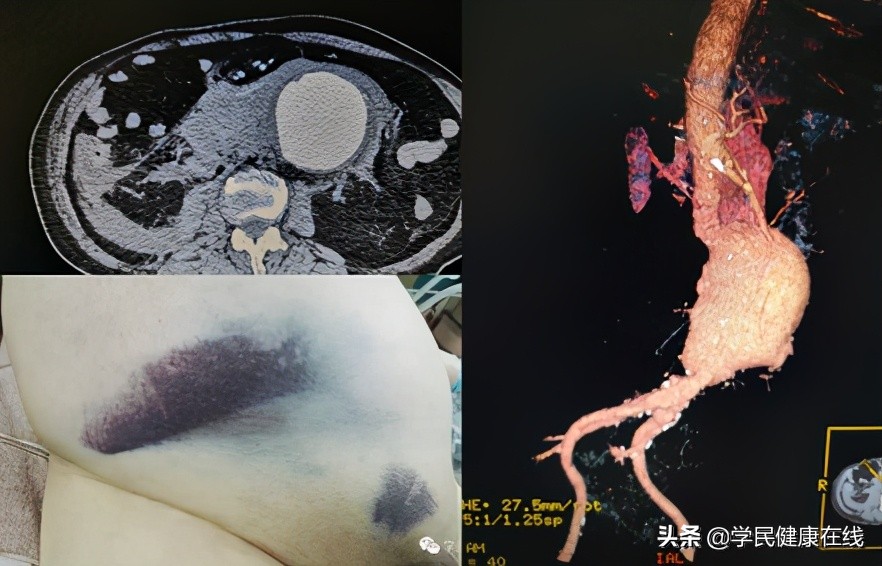

图1.破裂的腹主动脉瘤

后来出现了手术置换腹主动脉的技术,但主动脉是人体内最粗的动脉,这么粗的血管出了问题,人体自身没有合适的替代材料,曾经有人用同种异体的主动脉作为置换材料,但无法满足临床需求,直到人工血管的出现,使这种手术得以推广。但开刀手术创伤较大,术中出血较多,恢复较慢。而且腹主动脉瘤经常破裂之前没有症状,一旦破裂后,即便到达医院,接受外科治疗,死亡率也高达80%。其手术需要医院有强大的综合能力,国内一般只有大医院有能力开展。

从二十世纪八、九十年*开代**始,腔内覆膜支架植入作为腹主动脉瘤的治疗方案逐渐在全世界推广。这一技术是用支架把人工血管支撑在动脉瘤两端的正常血管段,在动脉瘤内重建正常口径的血流通道。这种技术可以把带人造血管的支架压缩在一个圆珠笔杆粗细的管道内,通过大腿根的股动脉,送入体内,在预定位置张开支架。由于术中不需要广泛解剖,可以采用局麻经过腹股沟切口或直接穿刺完成治疗。由于其微创,安全的特点和不高的技术门槛,目前腔内技术已经在一些基层医院得以推广。在更多患者受益的同时,这一技术的特有的并发症累积的数量也逐渐积累、增加,其中最主要的是内漏问题。所谓内漏就是指有持续性血流进入动脉瘤囊内,会导致瘤腔不缩小,甚至继续扩张,部分患者还可以破裂。